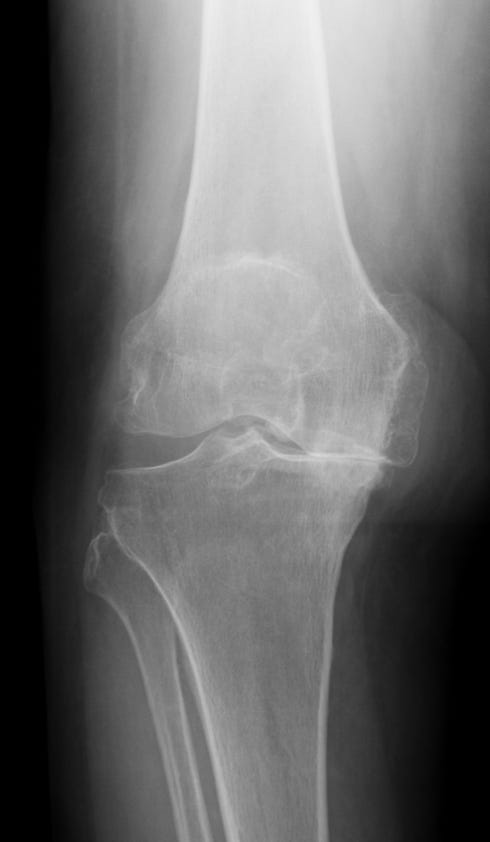

Artrosi ginocchio, gonartrosi

Artrosi del ginocchio

Complicanze delle protesi di ginocchio